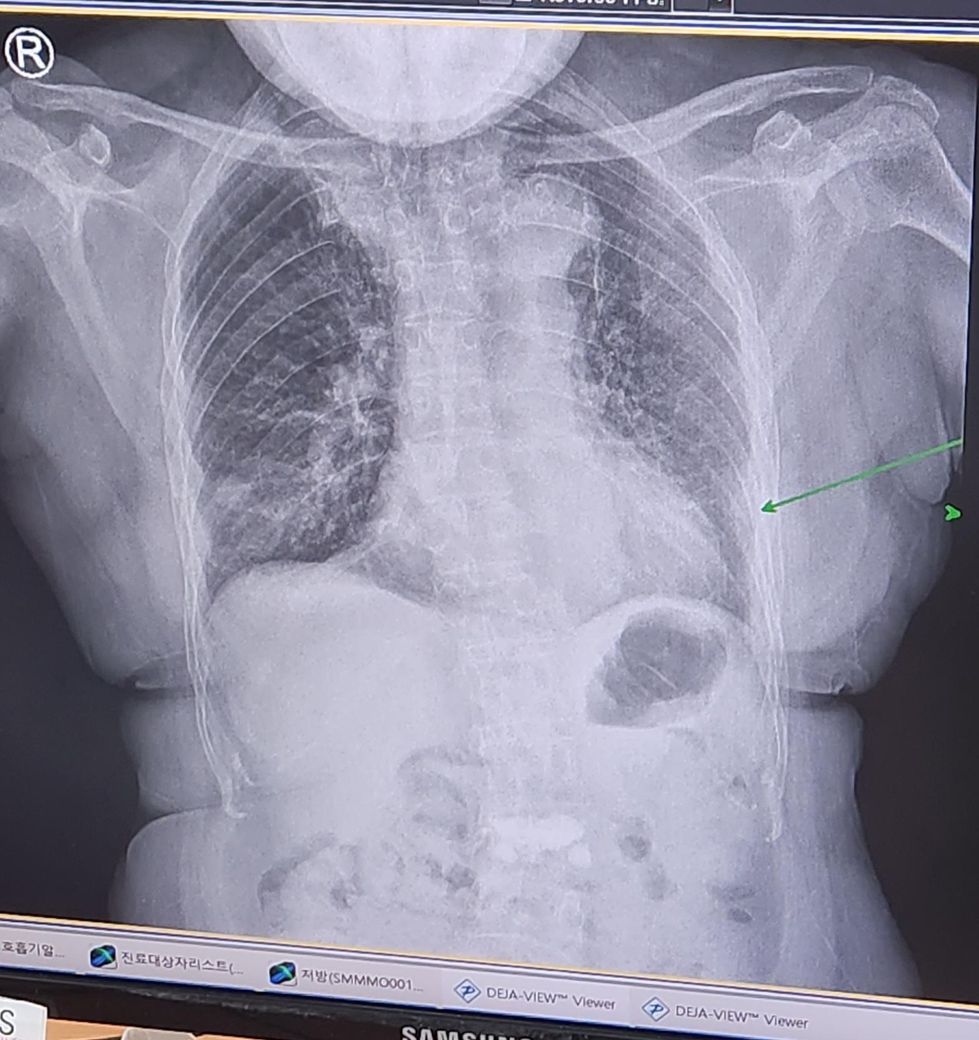

약 5일치먹고 다시가서 엑스레이찍으니

청진소리도 많이좋아지고 엑스레이상에서도

염증이 많이사라졌다하셨습니다.

조금 남았는데 약은 2일만 더 먹으라고 주셨고요

판정시 뽑은 피검사에서 염증수치 0.9였습니다.

아래가 5일후 엑스레이 입니다

4 아래사진에 초록화살표는 염증이 아닌건지요?

4 아래사진에 초록화살표는 염증이 아닌건지요? 폐렴끼는 아직 남아있어요